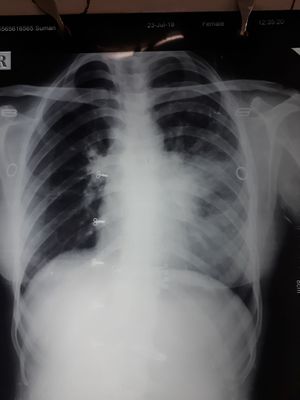

23 yr old female cough fever DOE 2 weeks

Left lower lobe consolidation in pneumoniae.

Loculated pneumonia left lower lobe

LLL PNA ...... looks like s/p intubation for surgical procedure